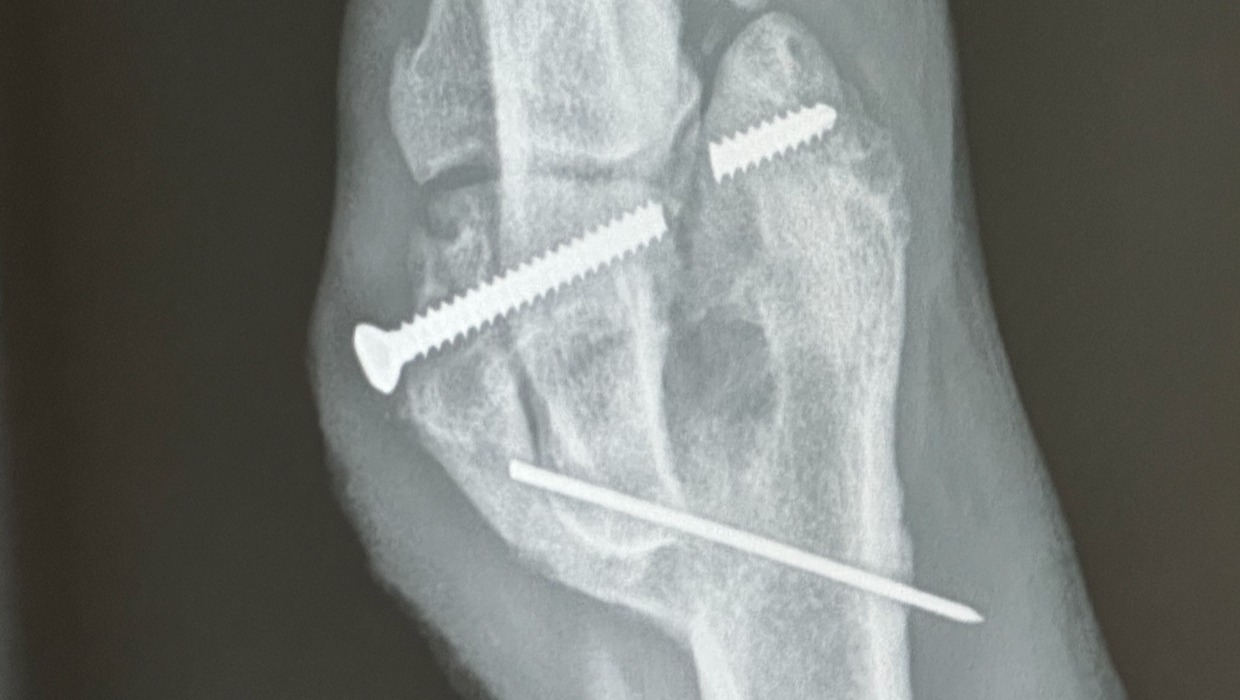

I took him to my vet the next day and discovered he currently has two broken screws in his elbow, one of which we believe is a drywall screw. This speaks very loudly to the care he was getting from his previous owner.

He has endured a great deal of pain for over a year despite only being 18 months old. The screws are protruding from his skin and restrict him from normal puppy activities. He can only go on short walks and needs breaks; stairs are difficult.

My family and I have decided that he deserves a chance at an everyday life, pain-free from his past. We have got him into an orthopedic surgeon specialist that will try to remove the screws that are not fused to his bone (see X-ray images attached).